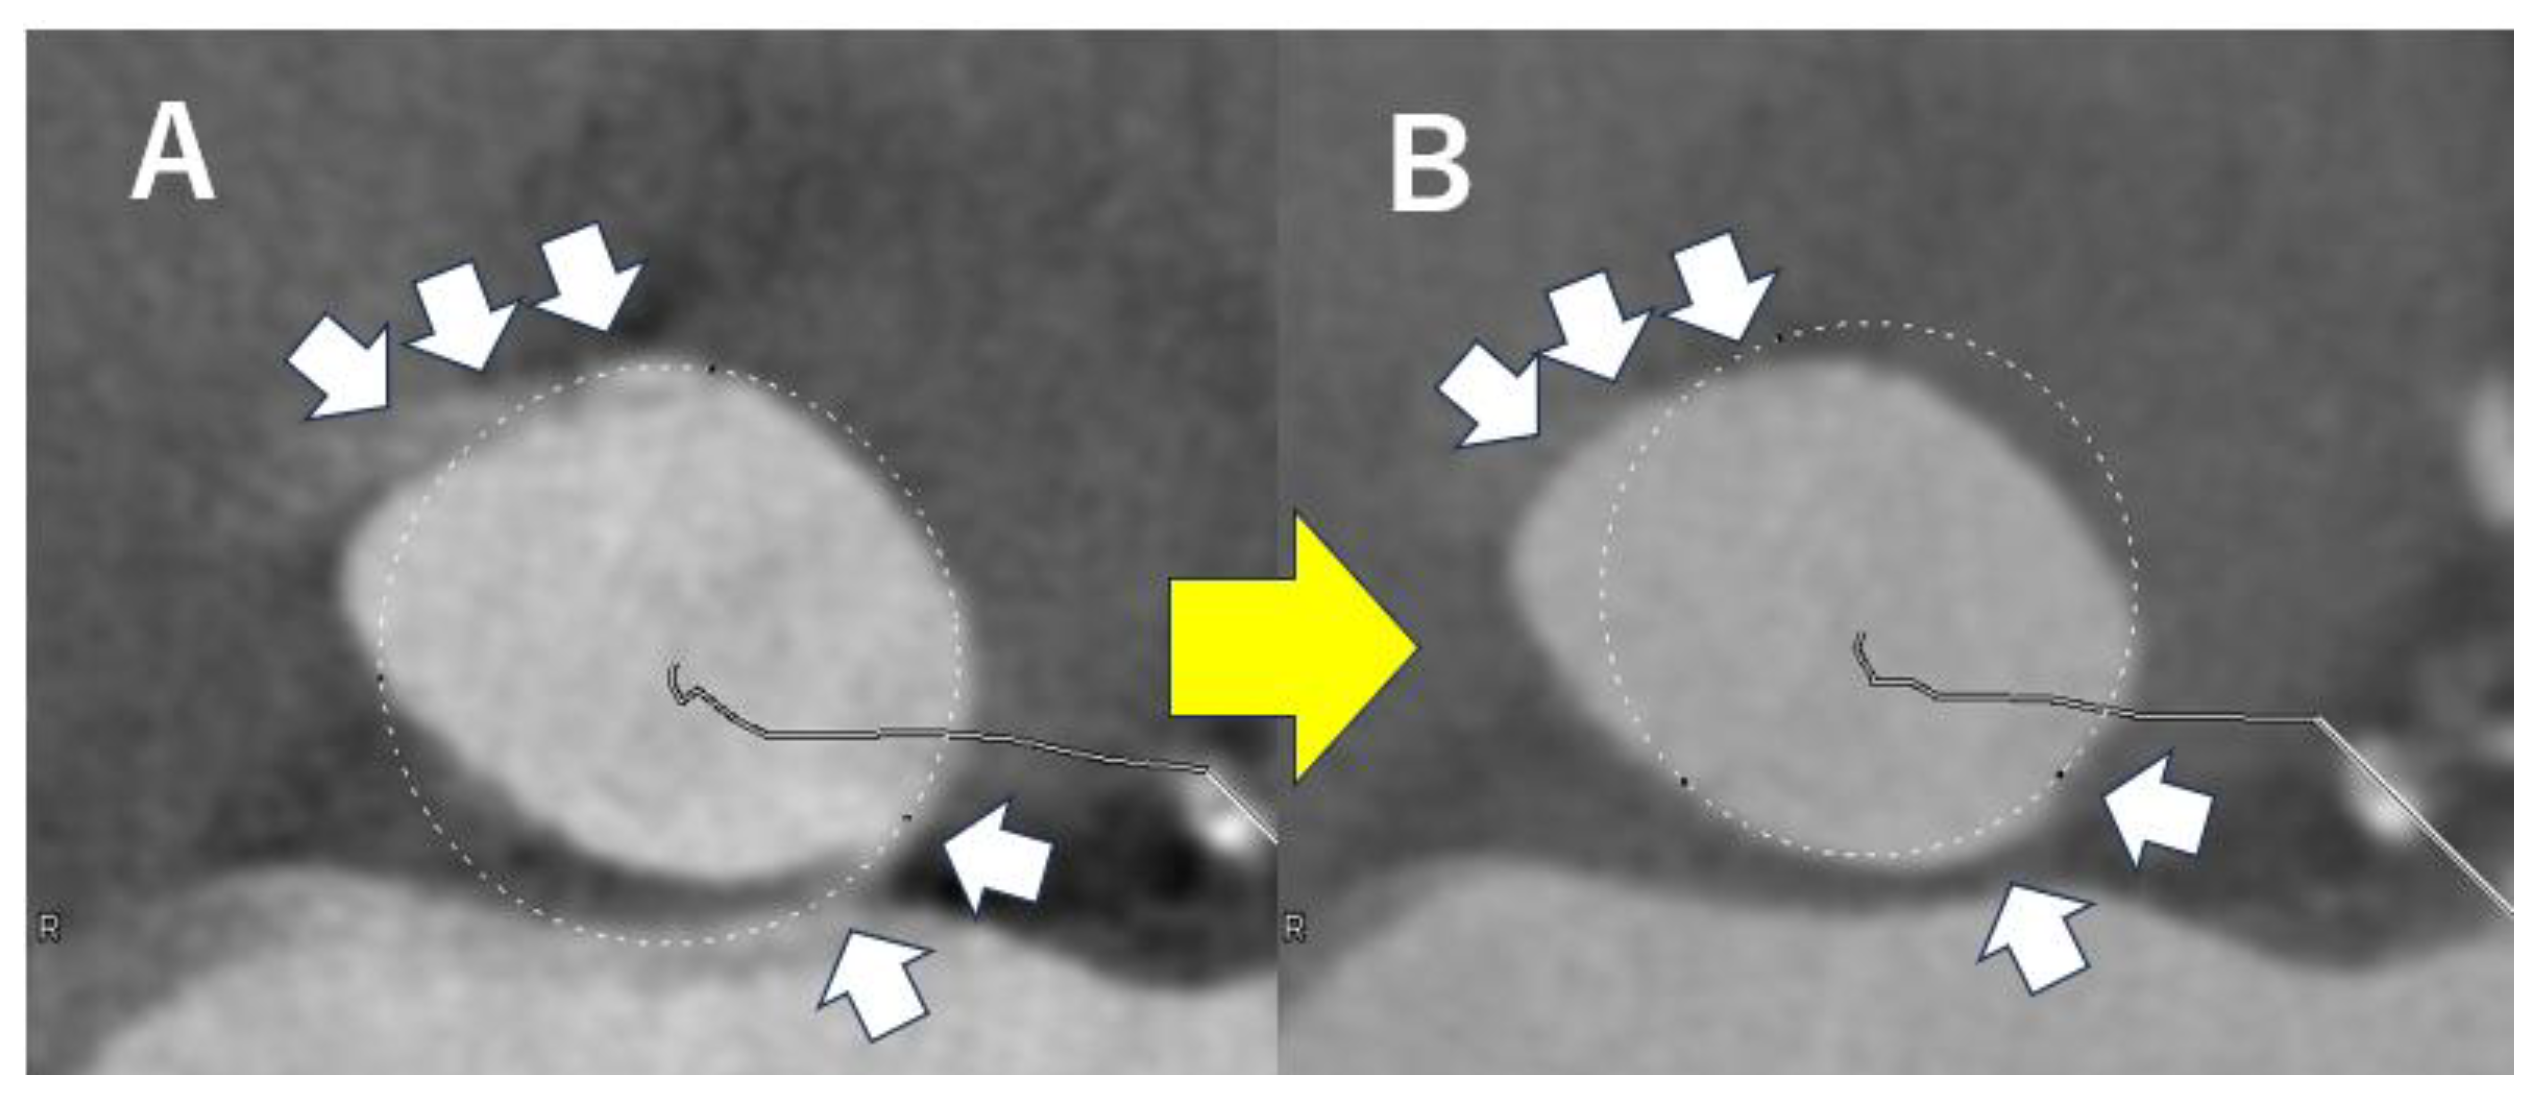

4.2. Analysis of Aortic Valve Complex on CT Before TAVI